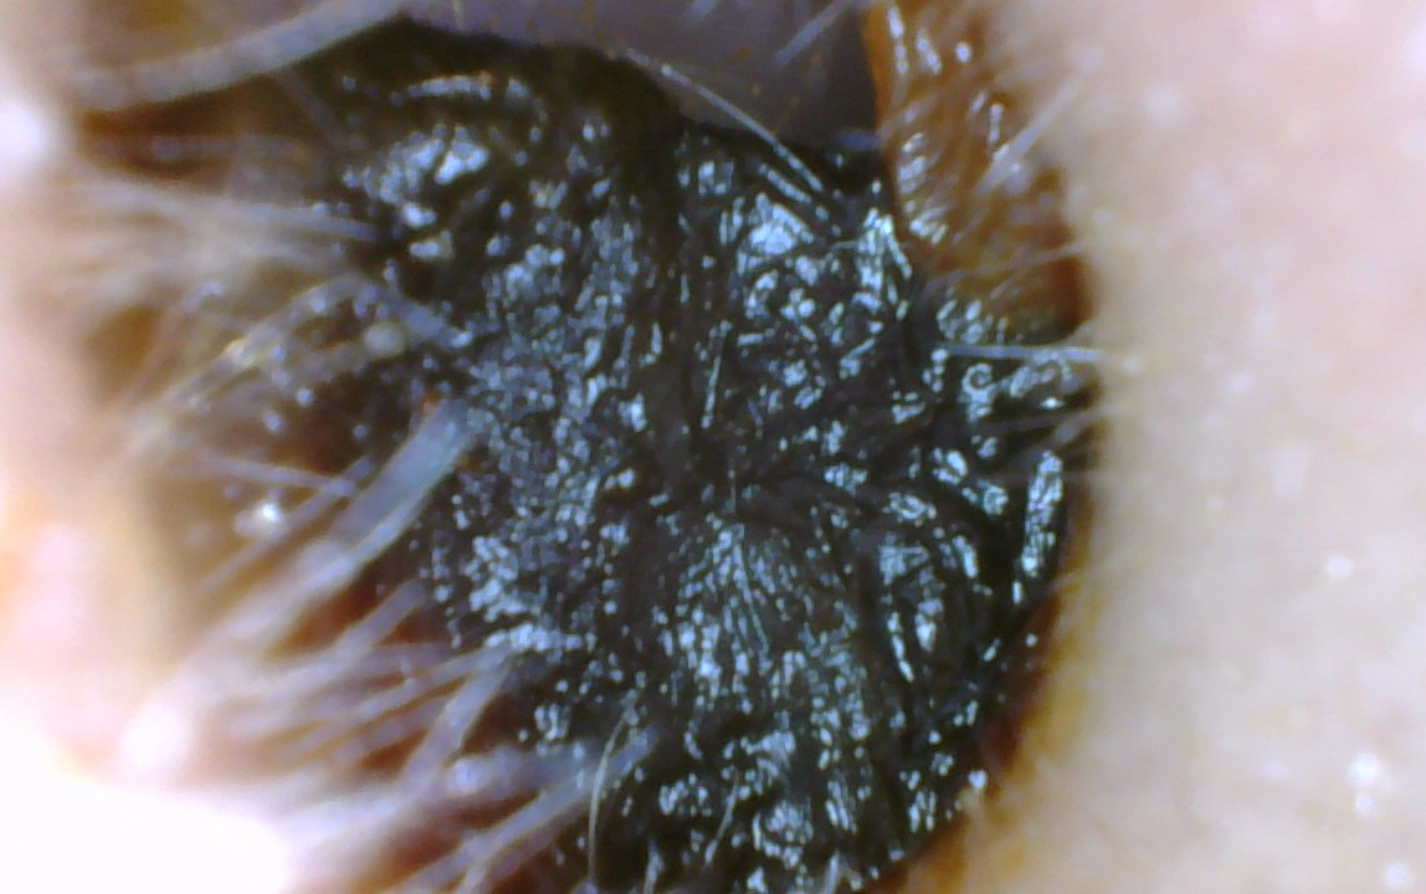

What Does an Earwax Blockage Look Like?

Before Removal: